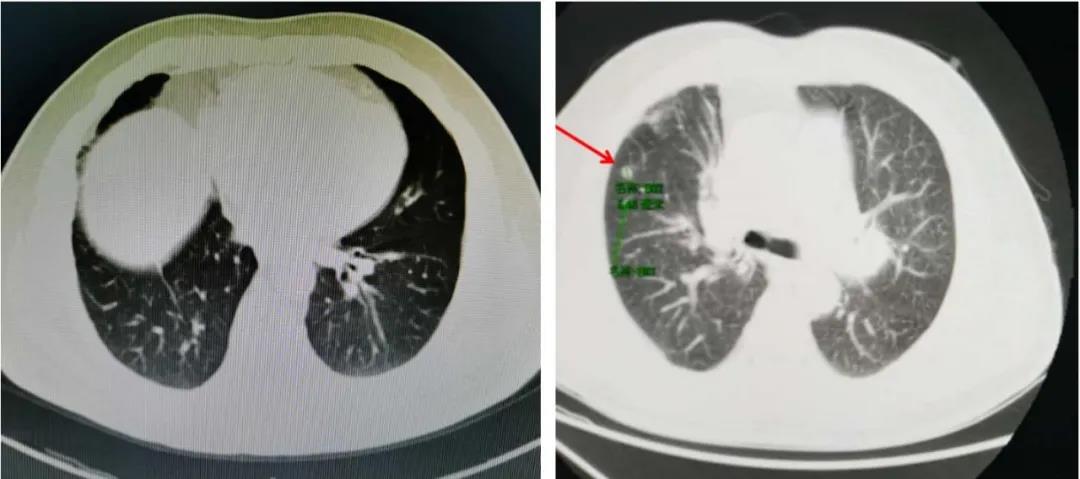

结合指南推荐与患者实际情况,一线治疗方案选择重组人血管内皮抑制素联合长春瑞滨+顺铂(NP)方案化疗4周期,疗效评价为CR。后续使用重组人血管内皮抑制素单药维持治疗29个周期。

2020年07月21日复查胸部CT提示疾病进展,患者PFS超过28个月。